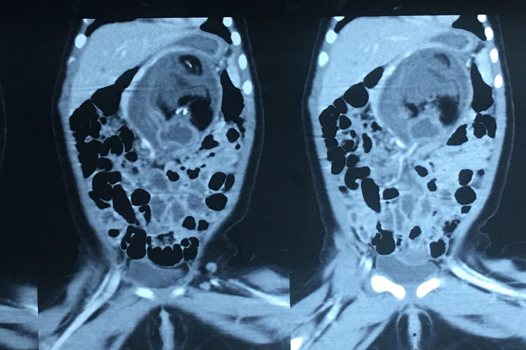

Foetus-In-Fetu (3)